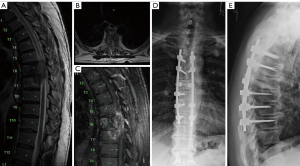

Anesthesia was lightened until lower extremity movement was confirmed. In the setting of acute neurologic change, the patient was fully awakened, extubated, and transported directly to MRI for emergent re-imaging. She had return of BLE neurologic function prior to MRI. During MRI, the patient experienced significant pain when positioned supine and required sedation to reduce motion artifact. Throughout imaging, intravenous steroids were provided and MAPs were maintained >85 mmHg. Once MRI was complete, neurologic examination identified BLE weakness: right lower extremity with 2/5 proximally and 3/5 distally; left lower extremity with 4/5 throughout. MRI demonstrated T10–T11 cord edema (Figure 1A-1C). The patient was maintained in 30-degrees flexion and steroids continued until she regained full BLE function on day 2. On May 10, 2023 she underwent T9–T11 laminectomy and fusion extension to T4 as indicated on ProAxis. With normal strength in flexion/thoracic kyphosis posture, the initial thoracic decompression was completed with ProAxis flexed to 30-degrees and slowly extended, 10-degrees sequentially with continuous neuromonitoring. During this time, the patient had spinal implants placed while flattening ProAxis to neutral position. No MEP or SSEP neuromonitoring changes were identified throughout the procedure. The patient awoke with full motor strength in her BLE.

The patient had an uneventful postoperative hospitalization, with some persistent numbness in both legs/feet. She was discharged on May 15, 2023 (postoperative day 5) without complication. Figure 1D,1E demonstrate standing anteroposterior (AP) and lateral full length radiographs at her initial postoperative visit. One year after surgery, she had mild persistent back pain and required a walker for ambulation, but all motor/sensory symptoms in her BLE had resolved. Unfortunately, she developed proximal junctional kyphosis with worsening back pain, and underwent extension of fusion to T1 with T3/4 Ponte osteotomies on October 1, 2024. She has been seen in clinic since that surgery with improved back pain and reduced reliance on her walker.